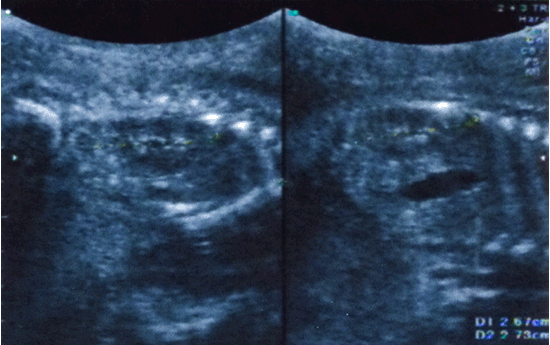

Hình 1. Hình ảnh thận hai bên bình thường ở siêu âm 26 tuần (sau truyền ối) |